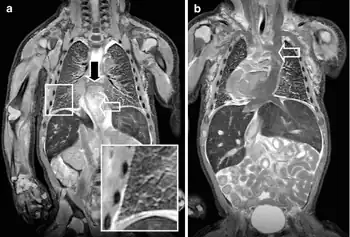

A neonate with a congenital cyanotic heart disease a)MRI shows a complete anomalous venous return b) T2-W coronal MRI shows a persistent left superior caval vein